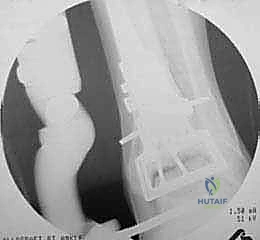

4. زراعة الطعم وتثبيته (Graft Implantation and Fixation)

- يتم تشكيل الطعم المأخوذ من المتبرع ليطابق الحفرة التي تم إعدادها في كاحل المريض تماماً (مثل تركيب قطعة البازل).

- يتم إدخال الطعم برفق (Press-fit).

- لضمان الثبات التام، يتم تثبيت الطعم باستخدام براغي دقيقة جداً (غالباً تكون قابلة للامتصاص البيولوجي أو براغي تيتانيوم غاطسة تحت مستوى الغضروف حتى لا تحتك بالمفصل).

5. إغلاق الجرح والتقييم النهائي

- يتم فحص حركة المفصل والتأكد من انسيابية السطح الغضروفي الجديد.

صور إضافية من داخل غرفة العمليات والخطوات الجراحية

ندرك أهمية توثيق الخطوات الجراحية لطلاب الطب والمرضى الراغبين في فهم دقة الإجراء. هذه الصور توضح مراحل زراعة وتثبيت الطعم العظمي الغضروفي بدقة متناهية تحت إشراف أ.د. محمد هطيف.